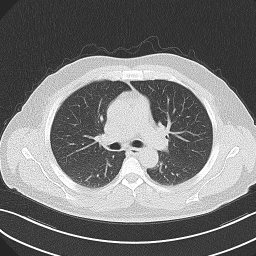

• Brain Tumor MRI Dataset (BMRI) [33]: The three datasets below are combined to create this dataset: figshare, SARTAJ, Br35H. There are 7023 MRI images of the human brain in this collection, divided into 4 categories: pituitary, glioma, meningioma, and no tumor. Images categorized as the ’no tumor’ class were obtained from the Br35H dataset.

• Chest X-ray Dataset (CXR) [34]: This dataset originates from the NIH, which is the largest chest radiograph data set. From 30,805 special patients, 112,120 frontal X-ray images are collected. Each X-ray is linked to the associated text disease label, which is drawn from the relevant radiological reports using an NLP algorithm.

• Lung Cancer CT Dataset (LCT) [35]: From different specialist hospitals, the IQ-OTH/NCCD lung cancer dataset was collected over three months in the fall of 2019. It comprises CT scans from patients with lung cancer in different stages and healthy subjects, totaling 1190 images from 110 cases. The dataset, marked by oncologists and radiologists, categorizes cases into three classes: normal (55 cases), benign (15 cases), and malignant (40 cases).

The proposed QMedShield’s security is evaluated using a number of metrics and proved that it is resistant to various cryptographic attacks including brute-force attacks, statistical attacks, histogram attacks, and differential attacks. Throughout the section, 6 sample medical images BMRI1,BMRI2,CXR1,CXR2,LCT1,LCT2𝐵𝑀𝑅subscript𝐼1𝐵𝑀𝑅subscript𝐼2𝐶𝑋subscript𝑅1𝐶𝑋subscript𝑅2𝐿𝐶subscript𝑇1𝐿𝐶subscript𝑇2BMRI_{1},BMRI_{2},CXR_{1},CXR_{2},LCT_{1},LCT_{2} are taken (2 images from each dataset) to show the performance comparison. The selection of MRI, X-ray, and CT images for the encryption task aims to demonstrate the versatility and effectiveness of our model across various imaging modalities, showcasing its applicability and robustness in diverse clinical scenarios. Figure 11 shows the selected sample medical images and their corresponding encrypted images.

Refer to caption

(a) BMRI1𝐵𝑀𝑅subscript𝐼1BMRI_{1}

(b) CXR1𝐶𝑋subscript𝑅1CXR_{1}

(c) LCT1𝐿𝐶subscript𝑇1LCT_{1}

(d) BMRI2𝐵𝑀𝑅subscript𝐼2BMRI_{2}

(e) CXR2𝐶𝑋subscript𝑅2CXR_{2}

(f) LCT2𝐿𝐶subscript𝑇2LCT_{2}

(g) E(BMRI1)𝐸𝐵𝑀𝑅subscript𝐼1E(BMRI_{1})

(h) E(CXR1)𝐸𝐶𝑋subscript𝑅1E(CXR_{1})

(i) E(LCT1)𝐸𝐿𝐶subscript𝑇1E(LCT_{1})

(j) E(BMRI2)𝐸𝐵𝑀𝑅subscript𝐼2E(BMRI_{2})

(k) E(CXR2)𝐸𝐶𝑋subscript𝑅2E(CXR_{2})

(l) E(LCT2)𝐸𝐿𝐶subscript𝑇2E(LCT_{2})

Figure 11: Selected sample plain medical images and the corresponding encrypted cipher images